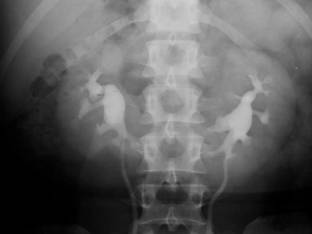

Fig. 61 – Duplicatie pielo-ureterala bilaterala incompleta

g. Duplicatia – poate fi bazinetala si/sau ureterala, completa sau incompleta.